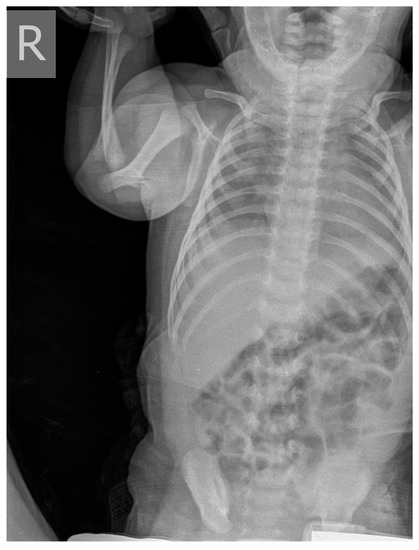

| Clinical picture at admission in Pediatric Clinic UCC | NN1 had a preserved sensorium, was high febrile 39.4 °C (rectal), with tachy-dyspnea, sobs, and moans, indents jugulum, dissatisfied cries, TM 4050 g, subclinical jaundice of the skin, and visible mucosa. Auscultation revealed attenuated respiratory sound, diffusely fine crackles, SaO2 82%, R 56/min, F 196/min. The umbilical stump persisted, the surrounding skin became red and swollen, there was hypotonia of the body axis, large fontanelle within the bony borders, greatness 20 × 30 mm. The other physical findings were normal. | NN2 had the preserved sensorium, was afebrile 37.7 °C (rectal), TM 3920 g, eupnoeic, presented sobs and moans, plethoric and icteric skin, nasal vestibules filled with seromucous secretion, and hyperemic throat. Auscultatory revealed a normal breathing sound is heard with transmitted wheezes from the upper parts of the airways and systolic murmur of 1-2/6 according to Levin, SaO2 97%, R 32/min, F 168/min. The umbilical stump persisted, thin, and the borders developed a serous–hemorrhagic discharge. There was mild hypotonia of the shoulder girdle and trunk axis, primitive reflexes were slowly elicited, large fontanelle was below the plane of the bony borders, and slightly spaced sutures, greatness 40 × 40 mm. The other physical findings were normal. |